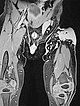

Coronal T2-weighted, fat-saturated MRI shows the tumor in the left groin as homogeneous and highly hyperintense (13 months of age) and clearly solid. Incidental findings include the soaked diaper, also with high signal intensity.

Same MRI sequence, coronal slice. The tumor is not only epifascial, but also shows a small subfascial extension under the fascia lata into the gluteal muscles. Thus, clearly infiltrative behavior.